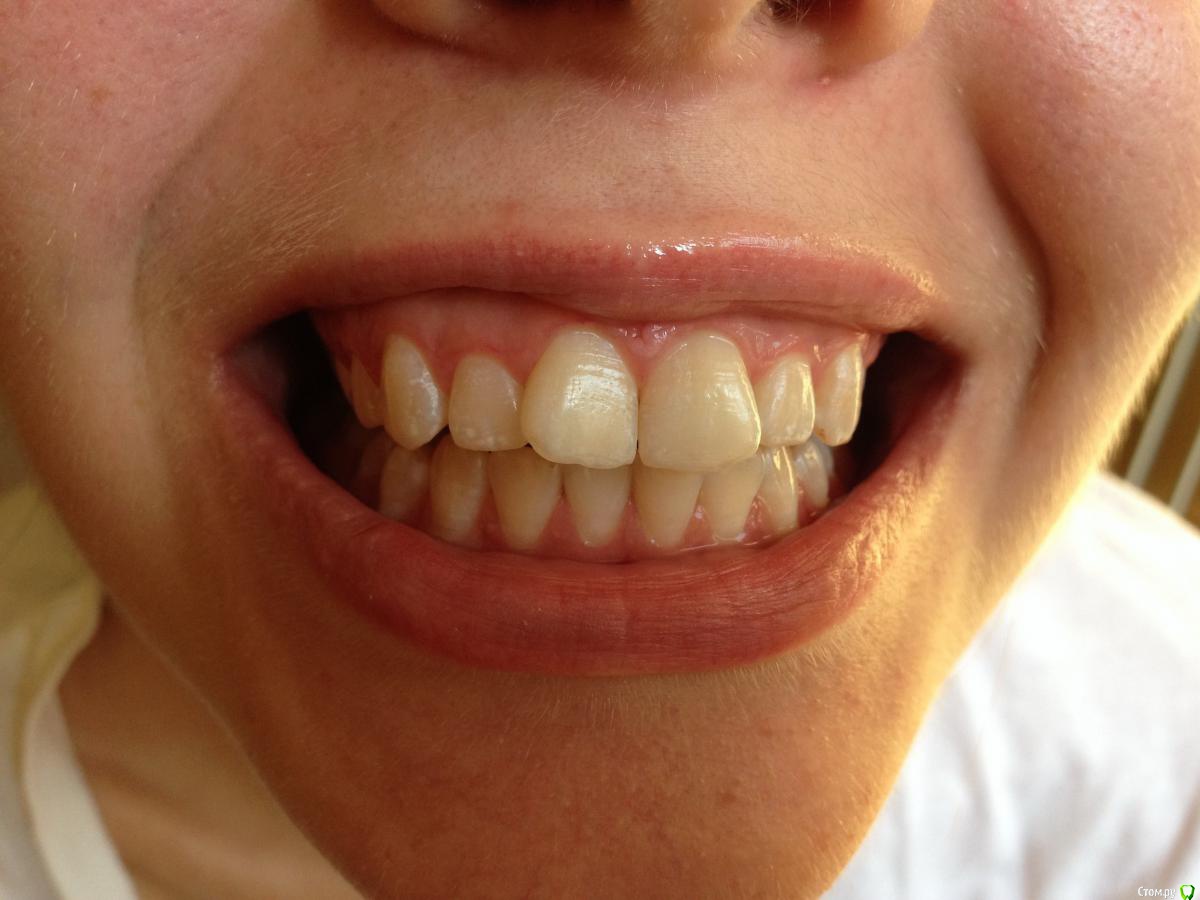

Ситуация следующая: сколько себя помню, всегда на зубах были белые пятна. Сейчас белые пятна почти на всех зубах и местами коричневые. Я не помню, когда появились коричневые пятна и очень беспокоюсь, что состояние эмали может в дальнейшем ухудшиться.

Врачи, у которых я консультировалась ставят разные диагнозы: флюороз, гипоплазия эмали. Рекомендуют наблюдаться и, к сожалению, не могут дать никаких прогнозов о развитии заболевания.

Фото зубов и снимок прилагаю. Буду очень благодарна за ваше профессиональное мнение.

Это у вас гипоплазия эмали вследствии флюороза, или так называемые крапчатые зубы. Что делать?, Ничего страшног просто участки с поврежденной эмалью очень хрупкие и поэтому выкрашиваются, просто пломбируйте, зато у вас устойчивостьт к кариесу повышенная